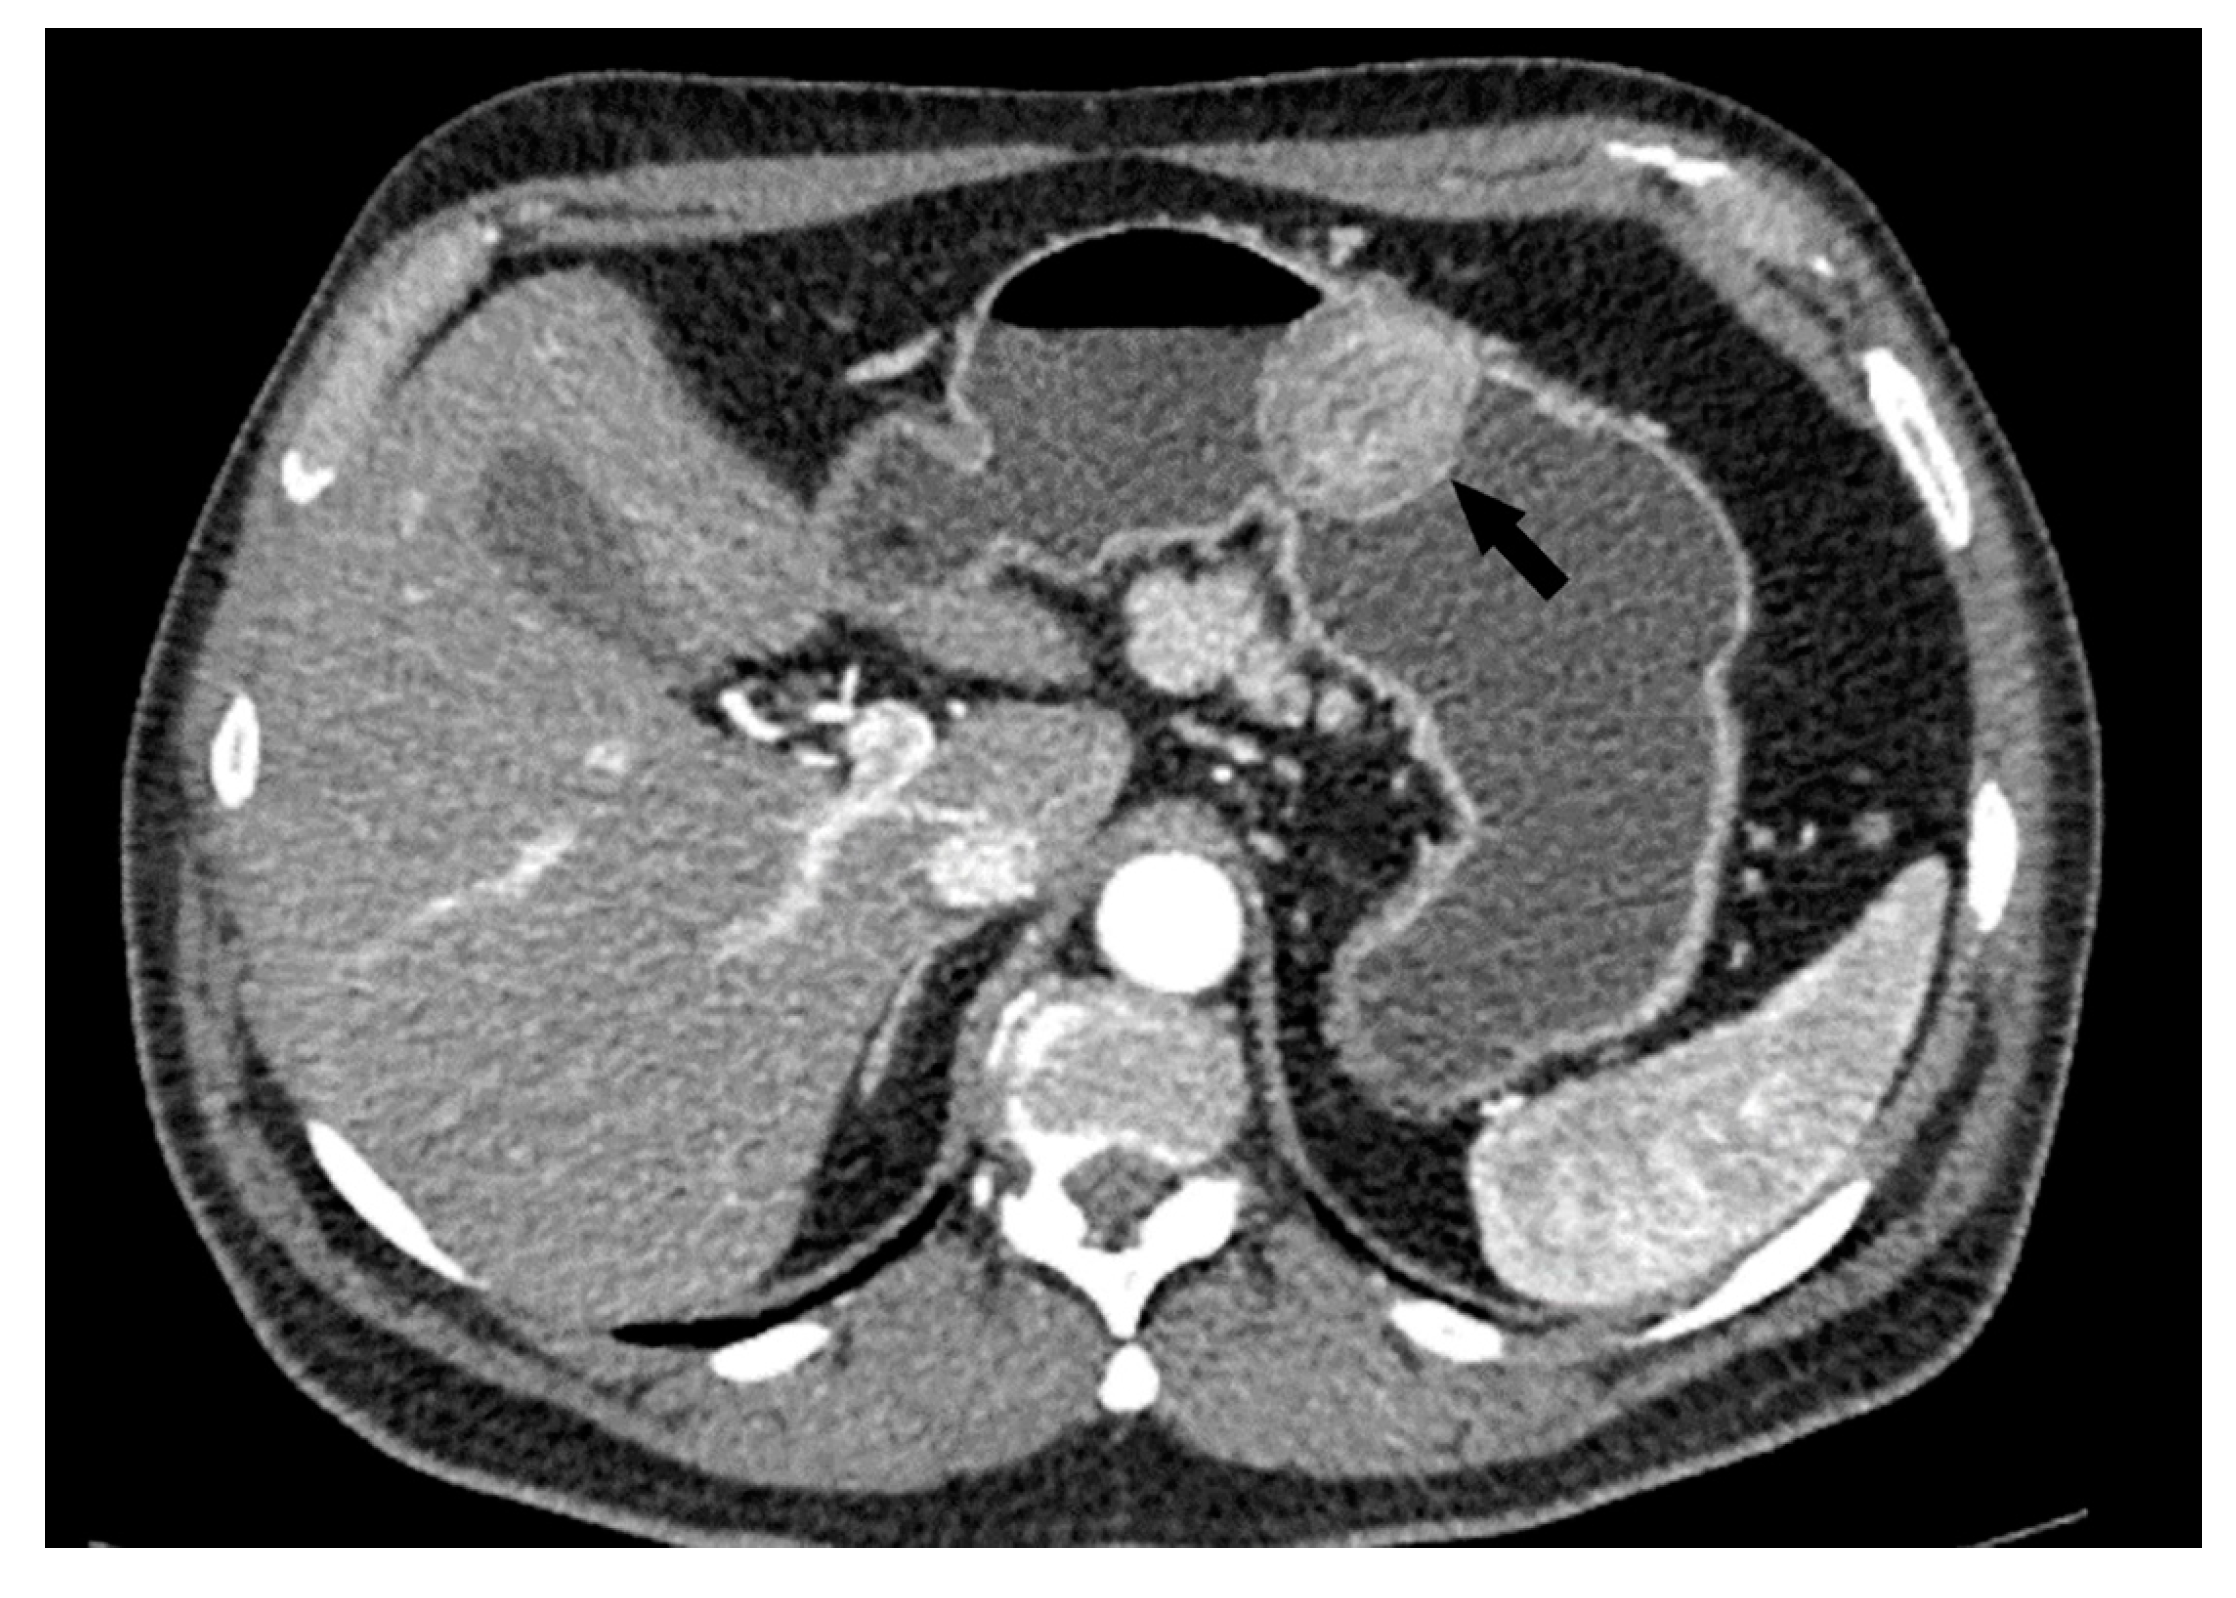

- Maximum diameter: the largest diameter of the tumor in mm (Figure 1);

- Tumor shape: regular or irregular (Figure 1);

- Growth mode: exophytic/mixed and endophytic (Figure 1);

- The presence of visible enlarged vascular structures draining/feeding the tumor (EFDV “enlarged feeding or draining vessel”) (Figure 6);